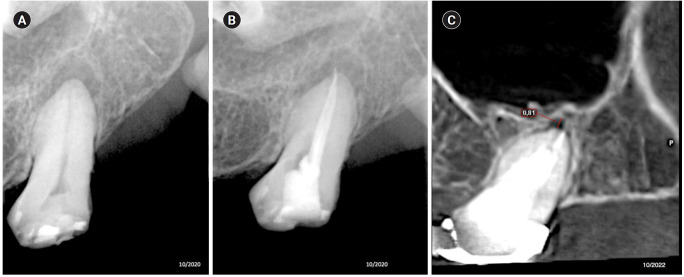

Methods: Teeth with apical lesions underwent endodontic treatment in which a high-power 810-nm diode laser with saline solution was used as monotherapy for disinfection. This type of therapy aimed to replace the traditional irrigation protocol with sodium hypochlorite. This research is the first to assess the clinical success of this alternative treatment, along with tomographic evaluations conducted over periods ranging from 2 to 7 years, analyzed using the periapical index based on cone-beam computed tomography (CBCTPAI). All cases were performed by a single clinician following the same laser protocol, which involved using 1 W of continuous power and four cycles of 20 seconds of laser activation.

Results: All teeth showed no clinical symptoms upon follow-up examination. However, the tomographic evaluation revealed that the success rates for teeth receiving primary treatment were 60% and 80% according to strict and loose criteria, respectively. For teeth requiring retreatment, the success rates were 12.5% and 37.5% using strict and loose criteria, respectively.

Conclusions: The teeth with apical lesions that underwent primary treatment did not present clinical symptoms, but they showed a moderate success rate on tomographic evaluation. However, despite lacking clinical symptoms, teeth with apical lesions that required retreatment had a very low success rate on tomographic evaluation.